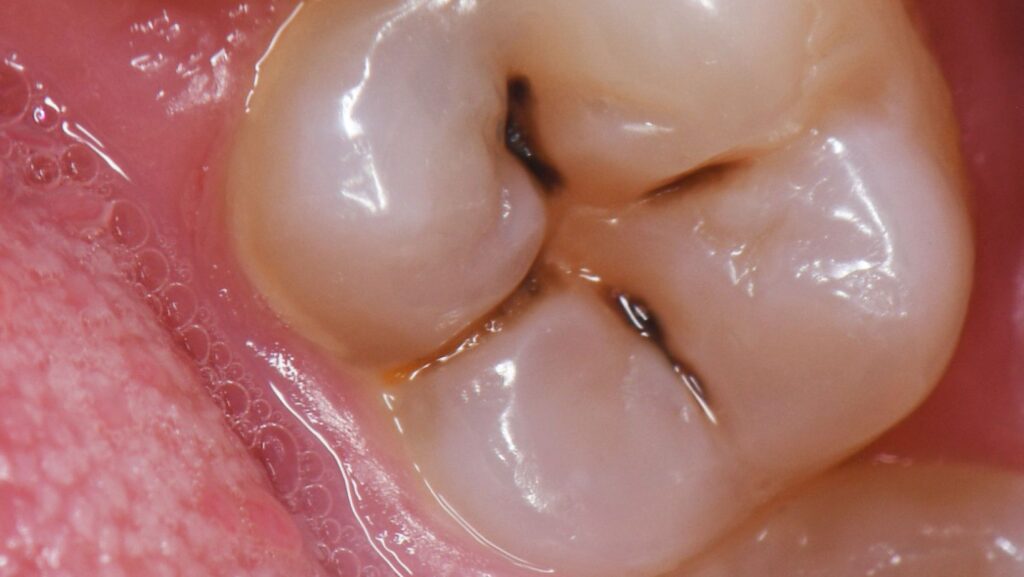

- The shape of your teeth

- The depth of your grooves and pits

Deep grooves, for example, make it much easier for bacteria to settle in — even with great brushing habits.

Some People Have More Cavity-Causing Bacteria

The bacteria Streptococcus mutans is one of the main culprits in tooth decay. Some people simply have more of it in their mouths, either through genetics, early exposure, or habits.

This bacteria thrives on sugar and produces acids that break down enamel. If you naturally have more of it, you’re at a higher risk — even if you brush well.